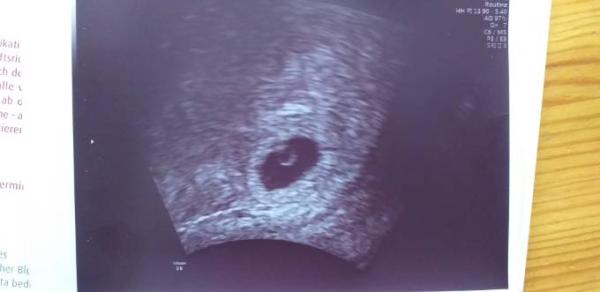

Huhu, Ich komme gerade vom Frauenarzt. Da ja bei mir das Risiko einer Eileiterschwangerschaft besteht musste ich wieder zum Ultraschall. Was soll ich sagen, ich bin schwanger, es sitzt wo es soll ( wie auch immer es in die Gebärmutter gekommen ist) und ein leichter Herzschlag war heute (5+4) schon zu erkennen! Es ist für mich total unwirklich und nicht zu begreifen. 6 Jahre Kinderwunsch, 3x erfolglose ivf, und jetzt bin ich einfach so schwanger geworden. Lieben Gruß Isaunddrei

Und das Bild ist ja toll